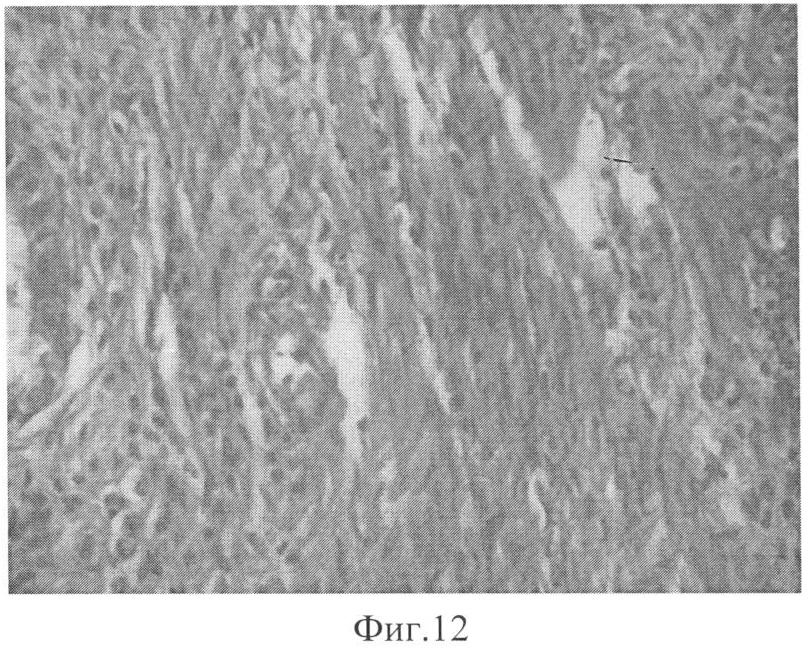

Изобретение поясняется фиг.1-12. На фиг.1 изображено бритье операционного поля, на фиг.2 – обработка антисептиком, на фиг.3 – разрез брюшной стенки, на фиг.4 – вход в брюшную полость, на фиг.5 – вывод матки в рану, на фиг.6 – наложение зажима и введение 5% раствора йода в правый рог матки, на фиг.7 – наложение зажима и введение 5% раствора йода в левый рог матки, на фиг.8 – возврат органов на свои места, на фиг.9 – ушивание раны, на фиг.10 – полная облитерация просвета матки (окр. пикро-сириус красным, ув. ×10), на фиг.11 – инфильтрация, зоны грануляций, рыхлая соединительная ткань (окр. гемотоксилин-эозином, ув. 8×20), на фиг.12 – коллагеновые волокна новообразованной соединительной ткани (окр. Мэллори, ув. 8×60).

На 14-е сутки крыса выводилась из опыта передозировкой эфирного наркоза, для морфологического исследования брали оба рога матки, препараты фиксировались в 10% нейтральном растворе формалина. Из полученного материала по общепринятой методике изготавливались срезы. Препараты окрашивали по Мэллори гемотоксилином и эозином, пикросириус красным и изучали в световом микроскопе под разными увеличениями.

При гистологическом исследовании отмечается полная облитерация просвета матки соединительной тканью, отмечается инфильтрация, зоны грануляций и новообразованные коллагеновые волокна.

Таким образом, разработанный нами способ моделирования внутриматочной адгезии является стандартизованным, легко воспроизводимым в опыте, максимально приближенным к условиям, возникающим в практике акушеров-гинекологов. Об этом свидетельствуют гистологические изменения: полная облитерация просвета матки соединительной тканью, инфильтрация, зоны грануляций и новообразованные коллагеновые волокна.